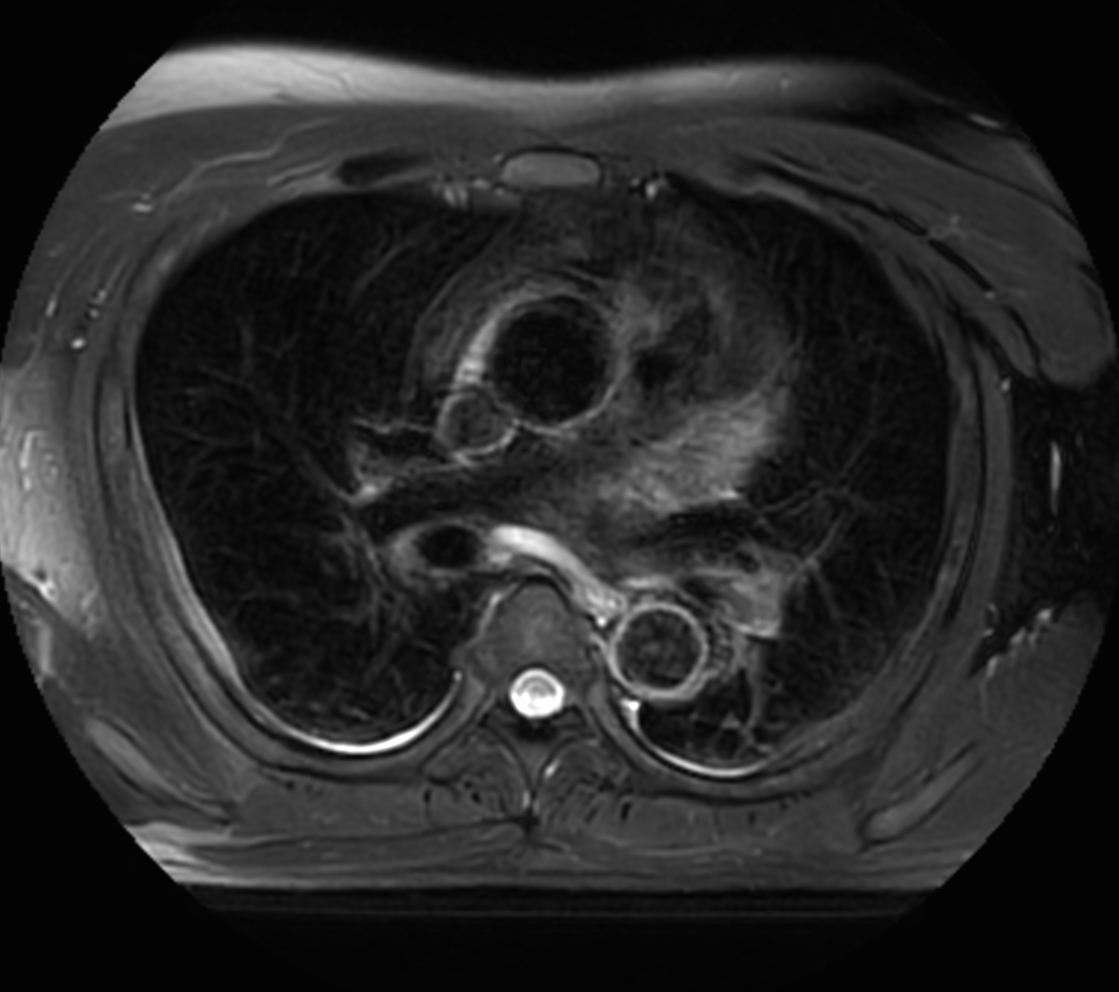

Axial MultiVane XD - T2w SPIR